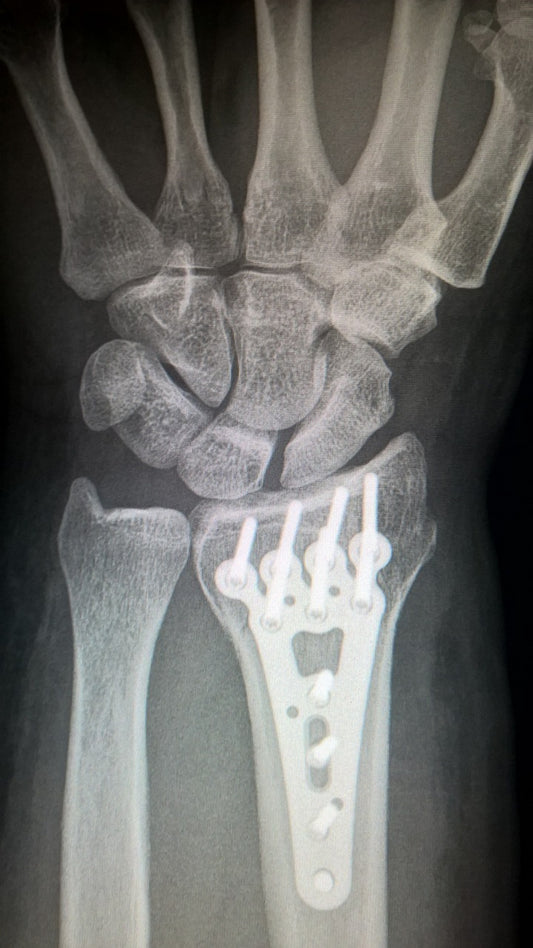

Radiografía de muñeca abierta y débil

¿Por qué se "abren" las muñecas? Causas y soluc...

Por qué se "abren" las muñecas después de años ejerciendo fuerza: Una mirada a la biomecánica y el envejecimiento Muchas personas que han pasado años ejerciendo fuerza, ya sea levantando...